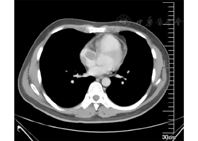

患者男,30岁,于2016年5月13日无明显诱因出现咳嗽、咳痰,咳白痰,量不多,伴咽痛,不伴胸闷、心慌,当地诊所诊断为上呼吸道感染,给予口服药物治疗,症状时轻时重。2016年6月10日出现心慌、胸闷,未诊治。2016年6月18日上楼时突发晕厥,意识丧失约5 min,急诊送至当地医院呼吸科。查体:心率136次/min,血压156/78 mmHg,呼吸23次/min,体温36.7℃,谷氨酸氨基转移酶184 U/L,天门冬氨酸氨基转移酶137 U/L,乳酸脱氢酶308 U/L,HBsAg(+), HBeAb(+),HbcAb(+),余未见异常。心电图示,窦性心动过速,V1导联RSR′图形,QRS电轴右偏,顺钟向转位。彩色多普勒超声示,大量心包积液,肺动脉外侧囊状回声,右心房内低回声(59 mm×48 mm)。胸部CT示,少量胸腔积液,头部右侧包块、右下腹包块,性质不明。抽取约100 ml血性心包积液,送检病理未见肿瘤细胞。2016年6月22日行PET-CT,示右肺下叶近肺门处不规则肿块,大小约32 mm×25 mm×24 mm,放射性摄取增高,最大标准化摄取值(maximal standard uptake value, SUVmax)为25.58;前纵隔上腔静脉旁不规则肿块,侵入右心房,大小约64 mm×54 mm×47 mm,放射性摄取增高,SUVmax为39.36(图1)。左前纵隔不规则肿块,与邻近大血管界限不清,侵及左肺上叶,大小约61 mm×62 mm×87 mm,放射性摄取显著增高,SUVmax为39.14,前上纵隔多发肿大淋巴结,直径约16 mm,放射性摄取增高,SUVmax为15.23,右侧颞部头皮下软组织肿块(SUVmax为50.09),右下腹壁皮下(直径约23 mm,SUVmax为5.80)、右侧阔筋膜张肌及右侧臀大肌多发软组织结节(SUVmax为15.93),双侧胸腔积液,心包积液;考虑淋巴瘤多系统侵犯。在CT引导下行前纵隔穿刺活检,免疫组化:CD10-,CD2(T+), CD20(-), CD23(-), CD3(T+), CD30(+), CD56(个别+), CD99(+), CD117(-), CD34(-),CD5(-) ,EMA(-), CK(AE1/AE3)(-), Ki-67(约85%+),Mum-1(+), Pax-(-), SALL(-), TdT(-),Granzyme B(+), LCA(+) ,EBER(-),变性淋巴瘤激酶(anaplastic lymphoma kinase, ALK) (+)。符合ALK阳性的间变性大细胞淋巴瘤。骨髓形态学、骨髓流式和骨髓活检均未见淋巴瘤侵犯。乙型肝炎病毒DNA低于检测下限,EB病毒DNA低于检测下限。诊断为非霍奇金淋巴瘤,ALK+间变大细胞淋巴瘤Ⅳ期,侵犯纵隔、心脏、右肺、右颞部、腹壁、臀大肌、阔筋膜张肌,国际预后指数(International Prognostic Index, IPI)评分4分,年龄校正的IPI评分3分。于2016年7月1日给予CHOPE方案化疗:依托泊苷0.1 g,第1~5天静脉滴注;环磷酰胺1.2 g,第1天静脉滴注;长春新碱2 mg,第1天静脉滴注;地塞米松30 mg,第1~5天静脉滴注;盐酸吡柔比星80 mg,第1天静脉滴注。2016年7月8日行彩色多普勒超声示,右心房内紧邻上腔静脉开口处可见约22 mm×27 mm的中等回声团块,其蒂附着于右心房壁,右心室流出道前壁向上延伸至肺动脉瓣环上方17.5 mm处的外侧,可见约55 mm×29 mm无回声团,内可见分隔;考虑囊性占位。2016年7月15日行彩色多普勒超声示,大量心包积液,右房内可探及23 mm×18 mm稍低回声团,与右心房壁相连,基底部宽约15 mm。于2016年7月29日、2016年8月18日分别给予EPOCH方案化疗:依托泊苷50 mg/m2,第1~4天静脉滴注;长春新碱0.5 mg,第1~4天静脉滴注;表柔比星15 mg/m2,第1~4天静脉滴注;环磷酰胺750 mg/m2,第5天静脉滴注;泼尼松100 mg,第1~5天静脉滴注。于2016年8月13日行增强CT示,右心房内、外各有软组织肿块,均较前缩小,前纵隔肿块较前缩小,右颞部及右下腹壁软组织肿块消失(图2);彩色多普勒超声示,右心房内实性占位(16.9 mm×18.9 mm),蒂宽10 mm,三尖瓣(轻度)反流。疗效评估达部分缓解,继续给予EPOCH方案(依托泊苷+强的松+长春新碱+环磷酰胺+阿霉素)化疗4个周期,期间行依托泊苷化疗后予以粒细胞集落刺激因子动员干细胞,顺利采集自体造血干细胞,移植前PET-CT评估疗效为不能确定的完全缓解,于2017年1月行自体造血干细胞移植,过程顺利。目前移植后3年余,病情稳定。